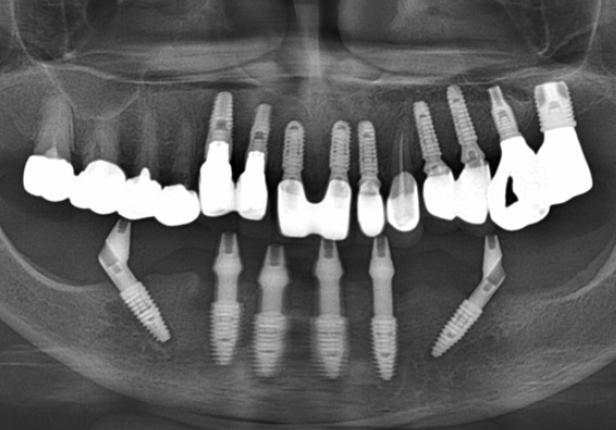

Mandibular Full case

Implant placement

AXA positioning

Post-surgery panorama